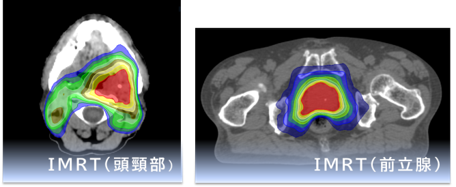

さらに当院では、体表面の形状を用いて位置や体動を確認するシステム(IDENTIFY) も導入しています。画像による確認に加えて体表面での確認も組み合わせることで、治療の安全性と再現性の向上に努めています。定位放射線治療(SRT・SBRT)や強度変調放射線治療(IMRT)など、病変や目的に応じた高精度治療にも対応しています。

近年の放射線治療の進歩は目覚ましく、「高精度放射線治療」といわれる、がん病巣へ正確に放射線治療を行いながら、かつ、がんの周囲にある正常組織にはあまり放射線を当てないよう工夫した治療ができるようになりました。